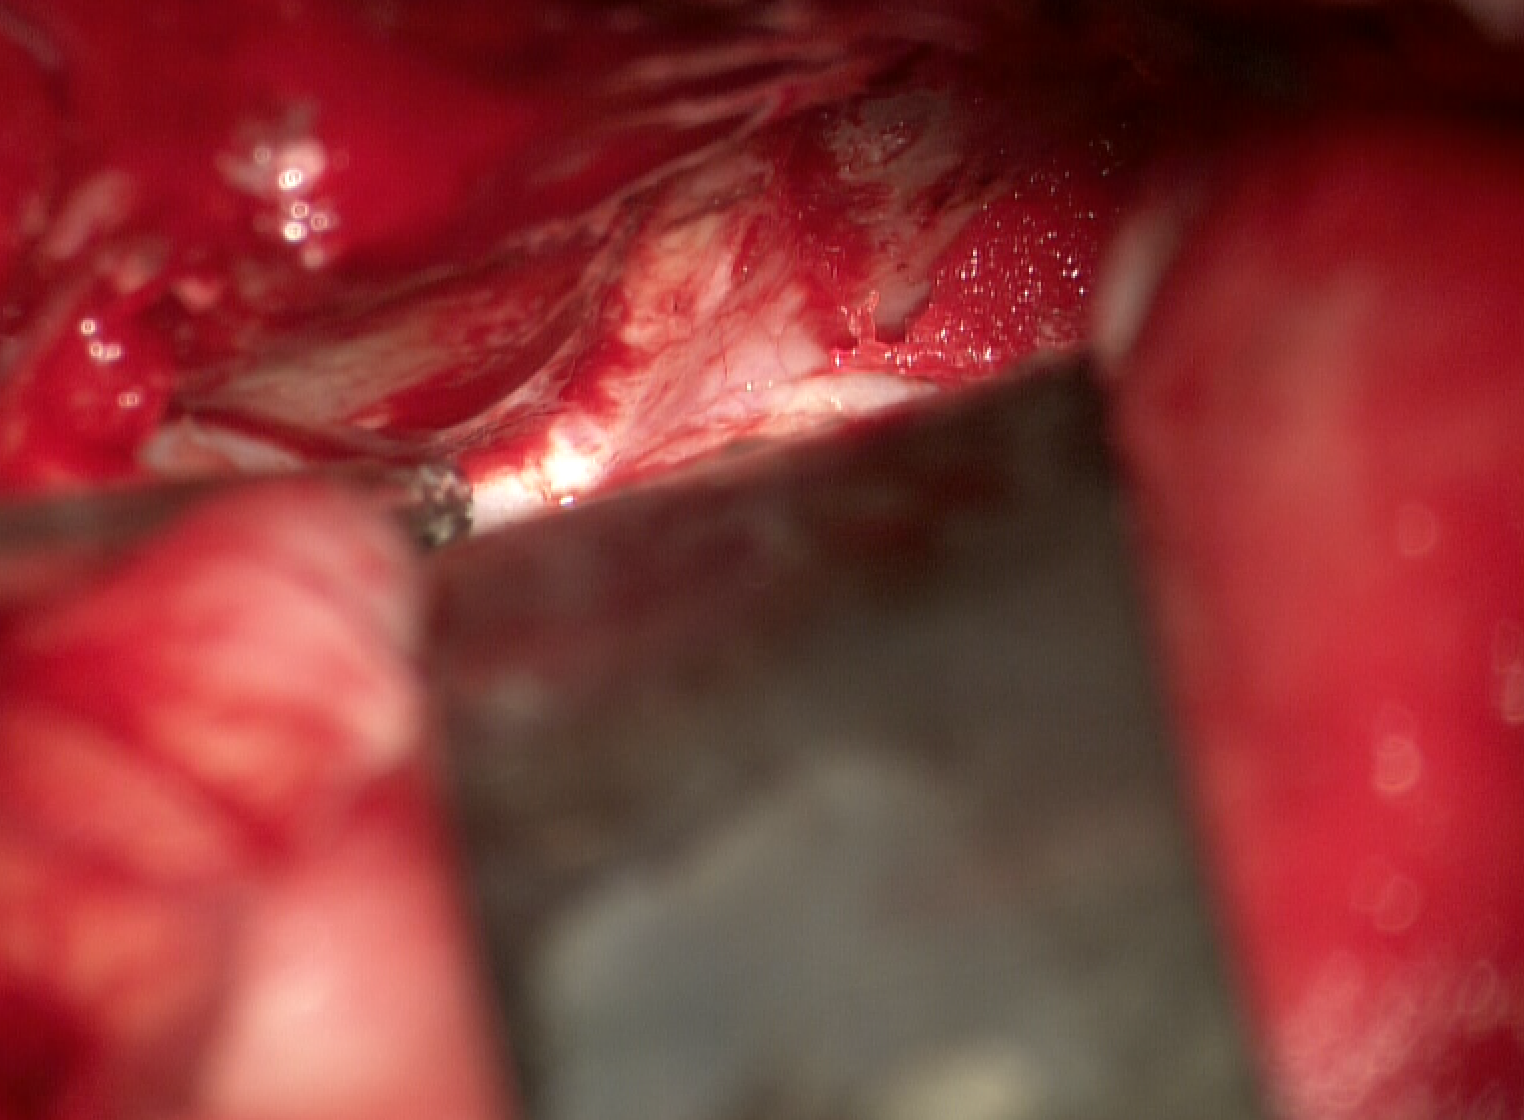

眼球破裂傷致失明兩天后才來就診

實(shí)在是太大意了,眼睛外傷失明兩天,剛剛晚上才過來檢查!虹膜嵌頓部分壞死,角膜血染,玻璃體也脫出來了,太嚴(yán)重了!連夜趕到湘雅醫(yī)院做手術(shù)去了!再一次溫馨提醒:這幾天天都有外傷的,眼睛周圍受傷了,一定要到醫(yī)院找專科醫(yī)生去檢查,沒有疼痛不代表沒有問題,皮外傷只是表面現(xiàn)象,一定要看眼球有沒有問題!